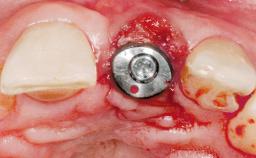

Immediate Placement of an Implant in a Maxillary Right Central Incisor Site

A 30-year-old female patient was referred to the office for the treatment of tooth 11. Her chief concern at the initial visit was to inquire, “Why is my tooth pink?” Upon clinical examination, it was determined that tooth 11 had a previous history of trauma and that the clinical crown had become noticeably pink in color as a result of internal resorption. This diagnosis was confirmed radiographically, indicating a large radiolucency involving the central and distal portions of the clinical crown. It was determined that restoration of this tooth was not possible, and that extraction was indicated. The presence of a mid-line diastema, which the patient wanted to reproduce, directed the treatment plan for tooth replacement utilizing a dental implant.

Type of Implants One-Piece|Reduced-Diameter

Bone Augmentation Horizontal|Simultaneous

Augmentation Materials Autogenous chips|Membrane